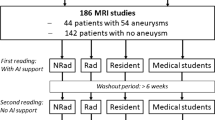

It is often time-consuming to segment fine structures, such as the cerebral arteries from magnetic resonance imaging (MRI). Moreover, extracting anatomically abnormal structures is generally difficult. The segmentation workflow called threshold field painting was tested for its feasibility in morbid minute artery segmentation with special emphasis on time efficiency.

Methods

Seven patients with meningioma with ten-sided feeding arteries (n = 10) originating from middle meningeal arteries (MMA) were investigated by three experts of the conventional method for segmentation. The MRI time-of-flight sequence was utilized for the segmentation of each procedure. The tasks were accomplished using both the conventional method and the proposed method in random order. The task completion time and usability score were analyzed using the Wilcoxon signed-rank test.

Except for one examinee (P = 0.06), the completion time significantly decreased (both P < 0.01) with the use of the proposed method. The average task completion time among the three examinees for the conventional method was 2.8 times longer than that for the proposed method. The usability score was generally in favor of the proposed method.